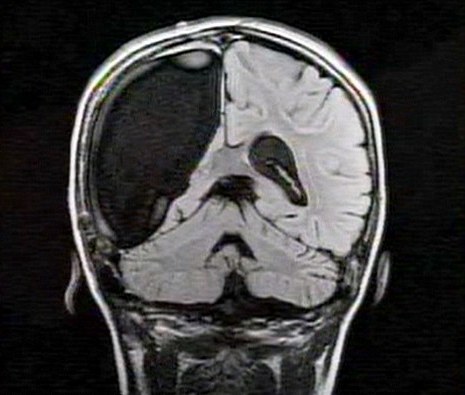

卡梅倫莫特在3歲那年患上一種被稱作大腦功能紊亂“拉斯穆森”綜合癥,這種病癥誘發(fā)患者的無序暴力行為和嚴(yán)重的癲癇。醫(yī)生建議,治療這種病癥只能通過嘗試消除引發(fā)此癥狀的大腦組織。而手術(shù)讓莫特失去了幾乎整個(gè)半邊的大腦。

據(jù)悉,莫特在手術(shù)后已經(jīng)可以跑動(dòng)和玩耍,她在術(shù)后的第四周離開了醫(yī)院。醫(yī)生表示,雖然右半邊大腦的切除可能會給莫特帶來半身不遂的風(fēng)險(xiǎn),但孩子剩余的大腦仍具有很強(qiáng)的重組和布線能力。